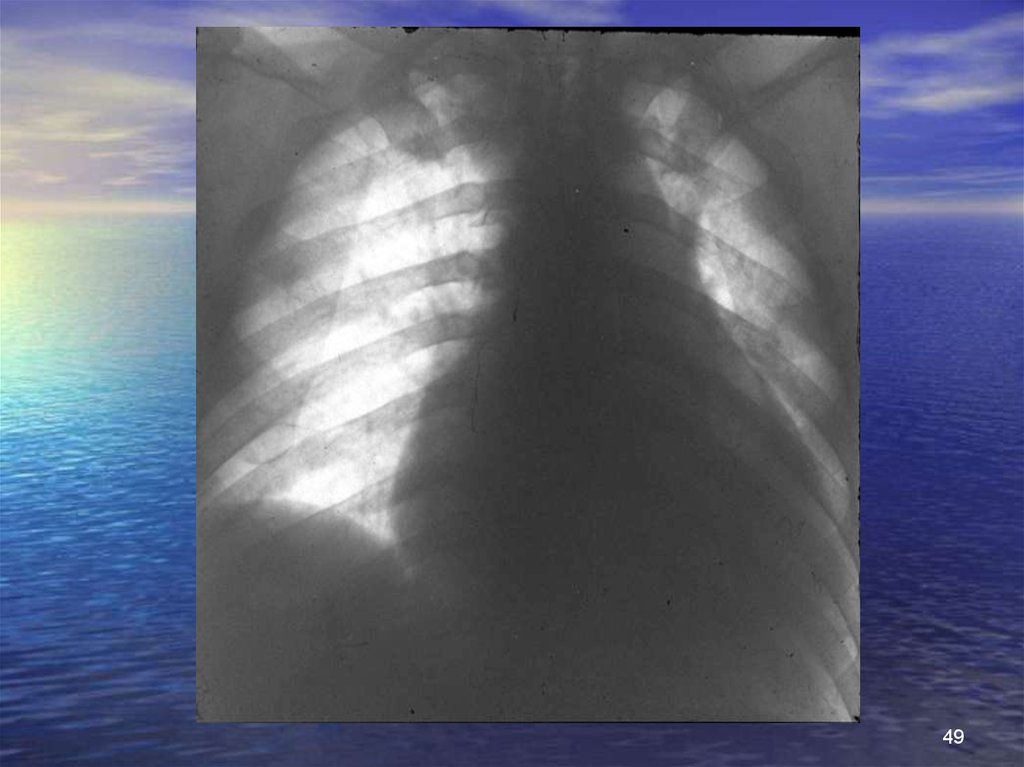

49.

49